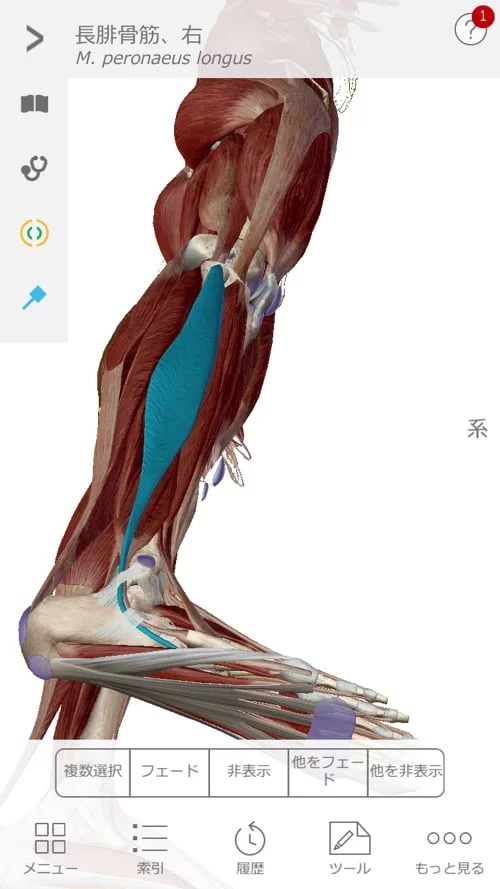

痛みの場所はここ。

そして脚の前側にも痛み

膝下のここにも痛み。

こんな感じで筋肉や腱の硬直やヨジレがありました。

今回のお客様はちょうどこんな感じで背中と太腿の筋肉が硬直していて

腰を上からも下からも引っ張っている状態。

痛みの主な原因はこの硬直によって骨盤が引っ張られてヨジレが生まれ

ヨジレた筋肉などが神経に当たって痛い。

それから骨盤から膝に繋がる筋肉。

そして膝から足の裏に繋がる筋肉。